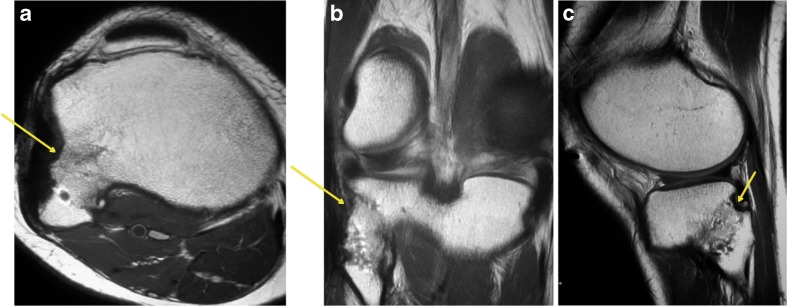

Fig. 5.

a, b, and c PD axial, coronal, and sagittal MRI images, respectively, of the patient in Case 1 after removal of hardware, demonstrating successful bony fusion of proximal tibiofibular joint (arrows point to the fusion site)